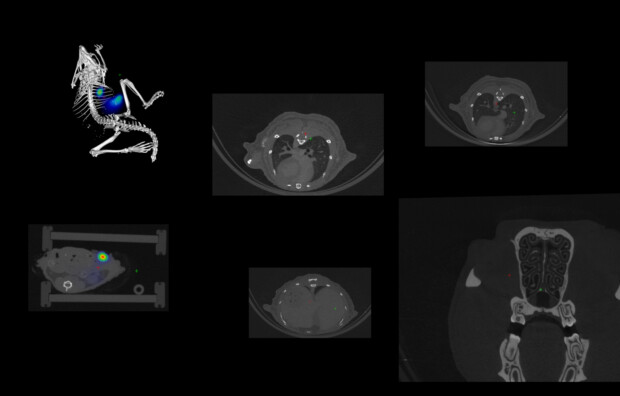

O LIEIV dispõe de uma infraestrutura física e de equipamentos para aquisição de imagens biológicas in vivo e ex vivo em modelos murinos e de humanos apta para atender às demandas investigativas de pesquisadores da UNIMONTES e de instituições de ensino superior (IES) parceiras, nacionais e internacionais.

No LIEIV, nos dedicamos a fornecer serviços de aquisição e análise de imagens biológicas de alta qualidade, visando resultados confiáveis previstos em projetos de pesquisa e de inovação de nossa clientela.